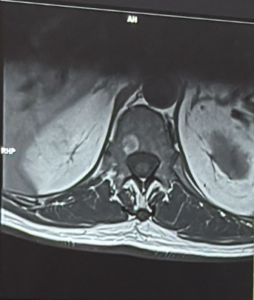

RM axial T1